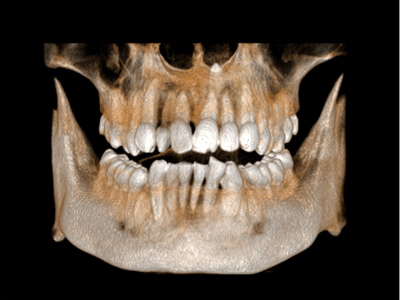

Pro Patient: Our state-of-the-art cone-beam computed tomography (CBCT) technology could selectively image the sinus, oral maxillofacial, para-nasal sinuses, ear & throat regions.

3D Imaging with Field of View sizes available in:

Proactive Dental Management thru our 3D Imaging Manipulation Software

With Oral Maxillofacial CT Scans, your dentist enhances his ability to proactively manage your health concern thru accurate diagnosis & better treatment planning. Moreover, the patient benefits from a painless,low radiation dose CT Scan procedure.